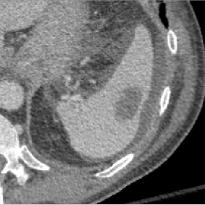

Early tumor detection save lives. Each year, more than 300 million computed tomography (CT) scans are performed worldwide, offering a vast opportunity for effective cancer screening. However, detecting small or early-stage tumors on these CT scans remains challenging, even for experts. Artificial intelligence (AI) models can assist by highlighting suspicious regions, but training such models typically requires extensive tumor masks--detailed, voxel-wise outlines of tumors manually drawn by radiologists. Drawing these masks is costly, requiring years of effort and millions of dollars. In contrast, nearly every CT scan in clinical practice is already accompanied by medical reports describing the tumor's size, number, appearance, and sometimes, pathology results--information that is rich, abundant, and often underutilized for AI training. We introduce R-Super, which trains AI to segment tumors that match their descriptions in medical reports. This approach scales AI training with large collections of readily available medical reports, substantially reducing the need for manually drawn tumor masks. When trained on 101,654 reports, AI models achieved performance comparable to those trained on 723 masks. Combining reports and masks further improved sensitivity by +13% and specificity by +8%, surpassing radiologists in detecting five of the seven tumor types. Notably, R-Super enabled segmentation of tumors in the spleen, gallbladder, prostate, bladder, uterus, and esophagus, for which no public masks or AI models previously existed. This study challenges the long-held belief that large-scale, labor-intensive tumor mask creation is indispensable, establishing a scalable and accessible path toward early detection across diverse tumor types. We plan to release our trained models, code, and dataset at https://github.com/MrGiovanni/R-Super